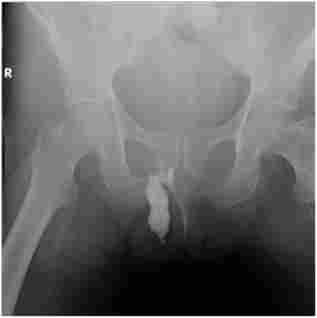

фістулографія (Рис. 15.1) - рентгеноконтрастное дослідження через зовнішній отвір свища. Введення в свищ рентгеноконтрастних, в тому числі водорозчинних, речовин (кардіотраст, йодоліпол, урографін і ін.) З подальшою поліпроекціонной рентгенографией - для виявлення зв'язку норицевого ходу з просвітом прямої або ободової кишки, що оточують її органами і тканинами. При цьому визначають напрямок норицевого ходу, його протяжність і розгалуженість. Методика часто використовується для диференціальної діагностики захворювань пара- ректальної клітковини і крижово-куприкової області (свищі прямої кишки, епітеліальні куприкова ходи).

Фістулографія (свищ прямої кишки з Параректальним затекло)

Мал. 15.1. Фістулографія (свищ прямої кишки з Параректальним затекло)

Введення контрастної речовини в свищевой хід здійснюється лікарем в рентгенівському кабінеті.